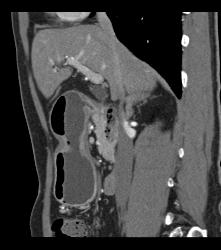

Antral Carcinoma